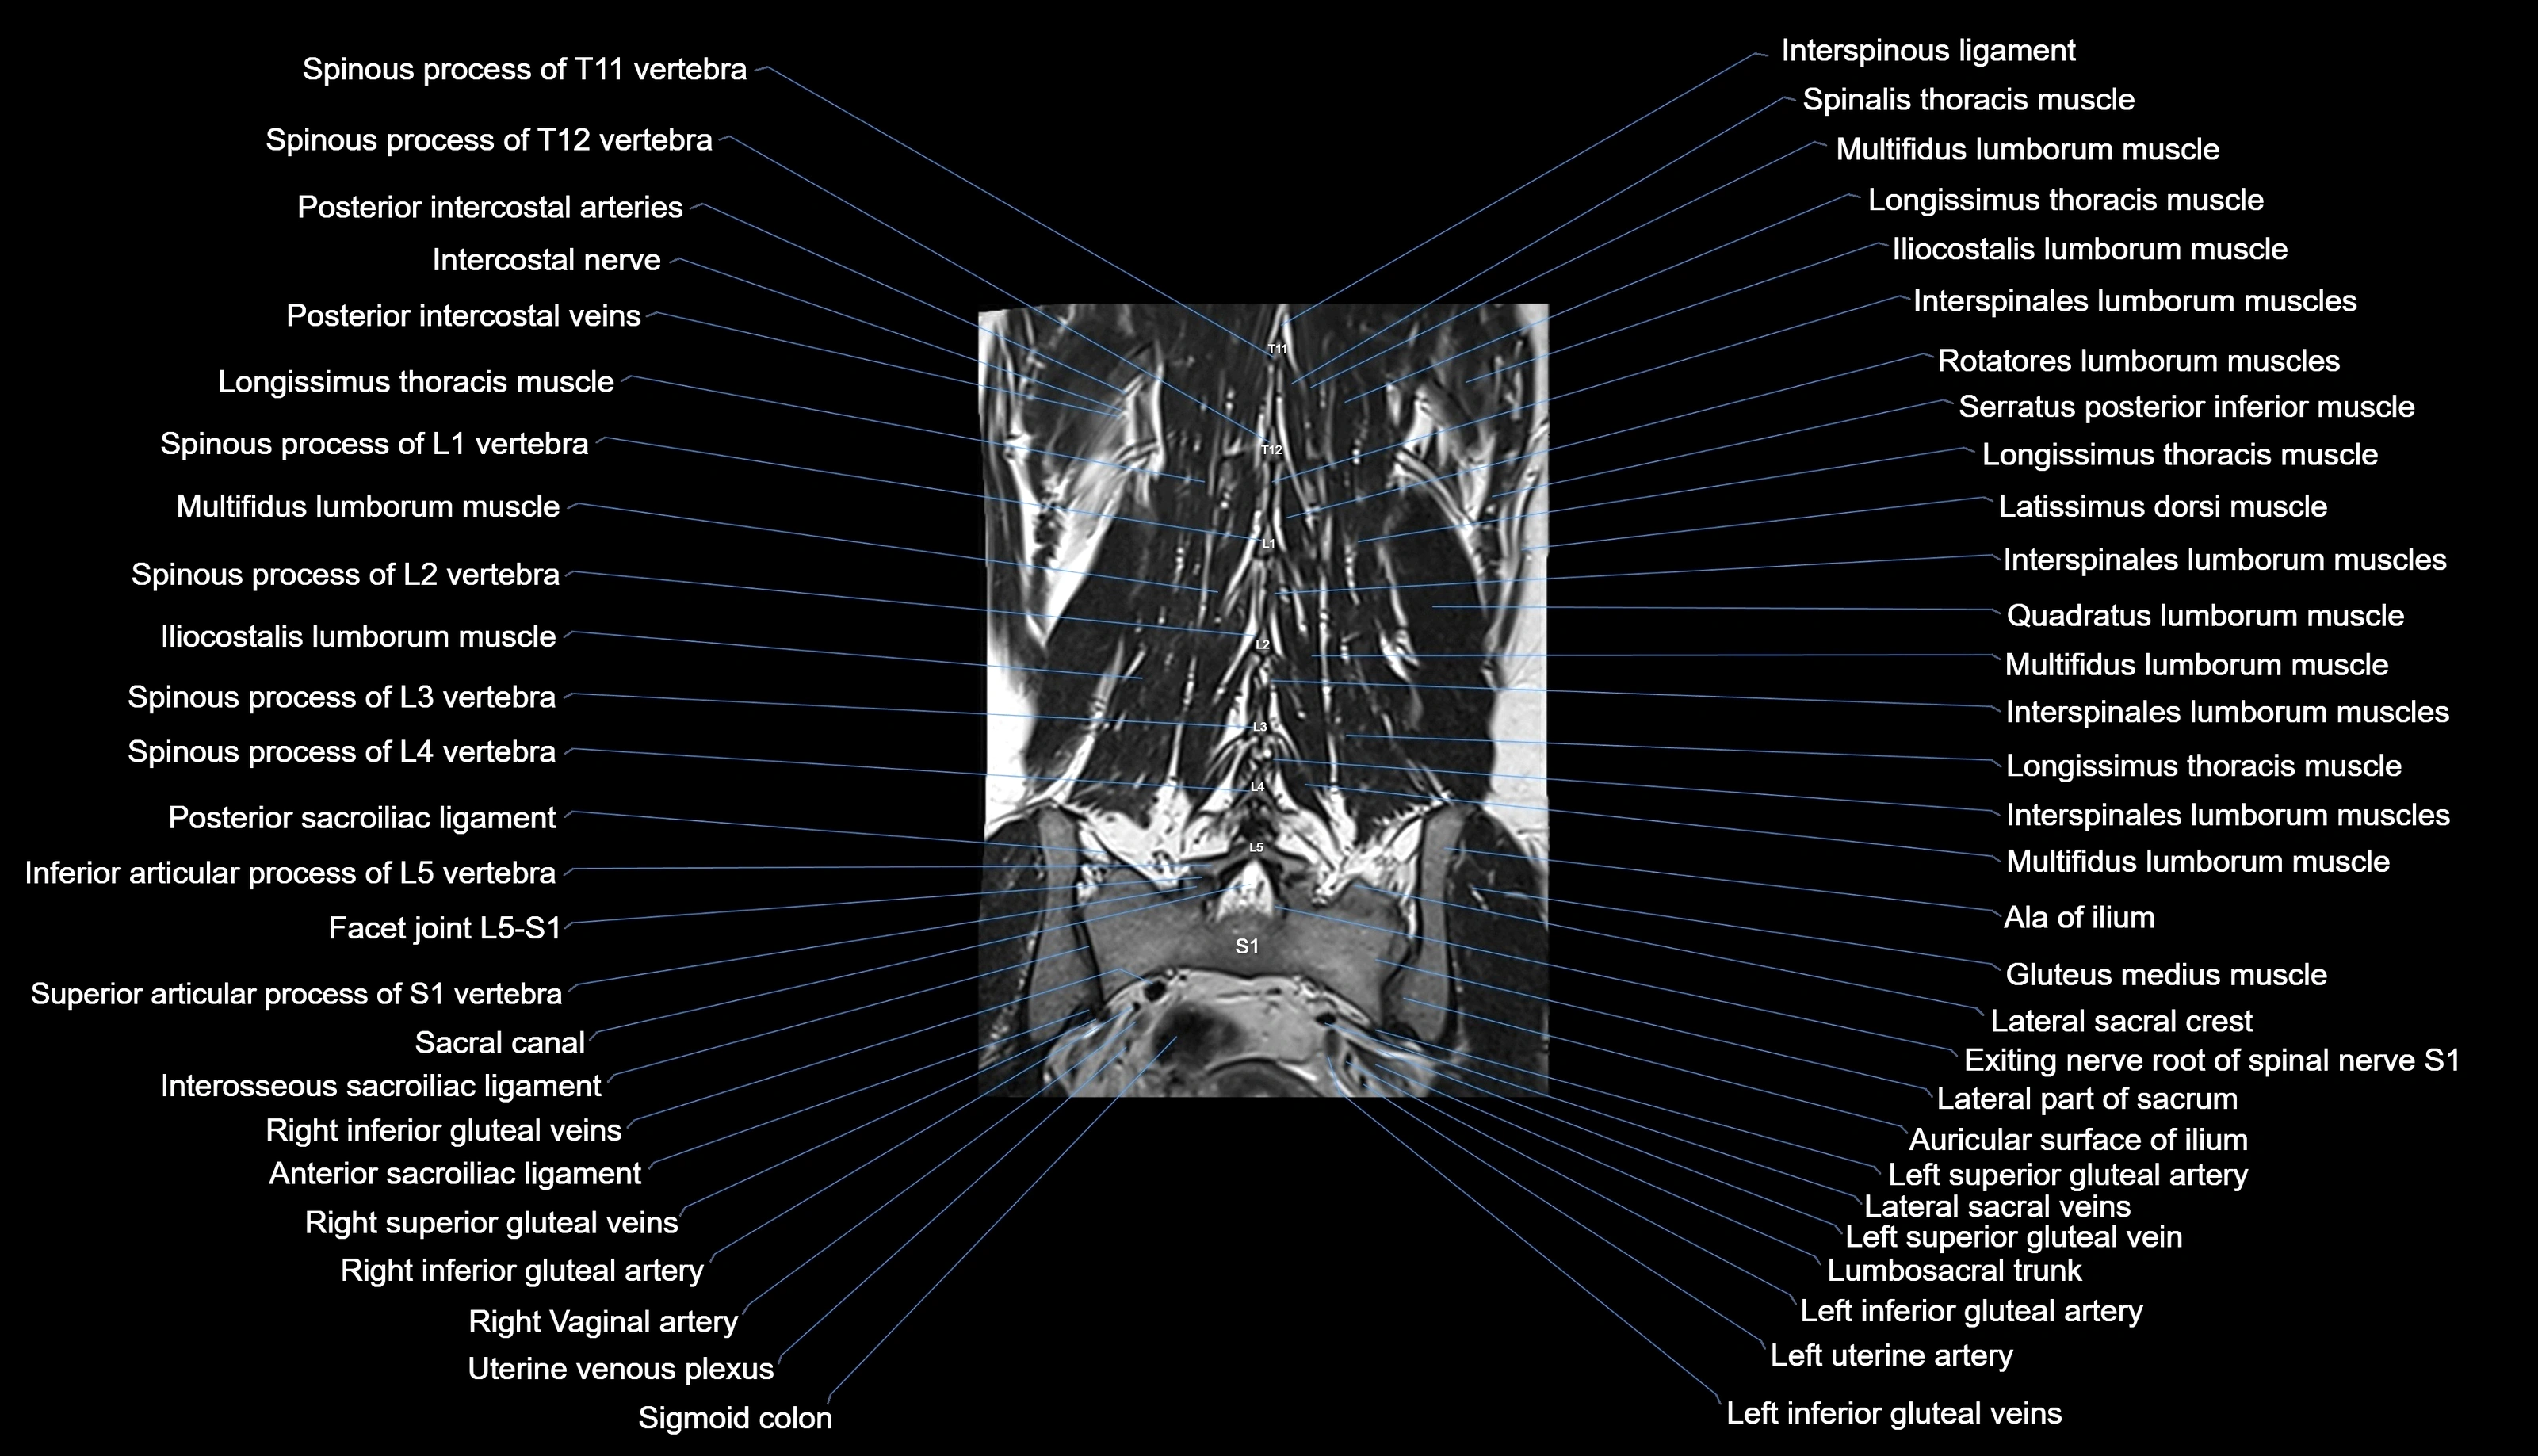

MRI images